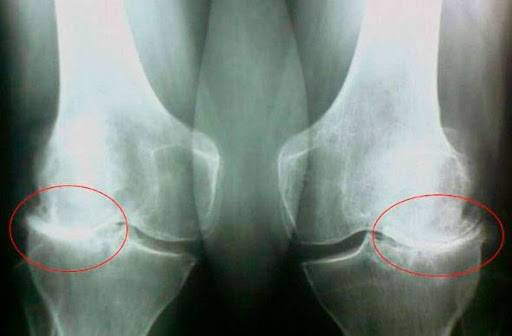

Δημήτρης Ευσταθίου: Λοιπόν, ο γιατρός είπε ότι αυτό είναι το τέλος. Και όχι μόνο για την καριέρα μου, αλλά και για τη ζωή μου. Δεν θα μπορώ να περπατήσω, θα παχύνω, ο διαβήτης μου θα επιδεινωθεί και αυτός είναι ουσιαστικά ο τάφος. Βρίσκομαι στο νοσοκομείο και κοιτάζω το ταβάνι... Είναι σαν να κοιτάζω το καπάκι ενός φέρετρου. Νόμιζα ότι θα πέθαινα σε αυτόν τον θάλαμο. Ο γιατρός επέστρεψε, άρχισε να μιλάει για επεμβάσεις στο Ισραήλ, στη Γερμανία, για εμεμβάσεις, για ΕΚΑΤΟΜΜΥΡΙΑ ΕΥΡΩ. Τότε συνειδητοποίησα ότι απλώς προσπαθούσε να με εξαπατήσει και δεν ήθελε να με θεραπεύσει. Θα πέθαινα ούτως ή άλλως από αυτόν τον πόνο στις αρθρώσεις. Κοιτάζω τις φωτογραφίες και συνειδητοποιώ ότι οι αρθρώσεις είχαν σχεδόν καταστραφεί. Ήμουν στα πρόθυρα του θανάτου. Αλλά μετά έγινε το θαύμα...